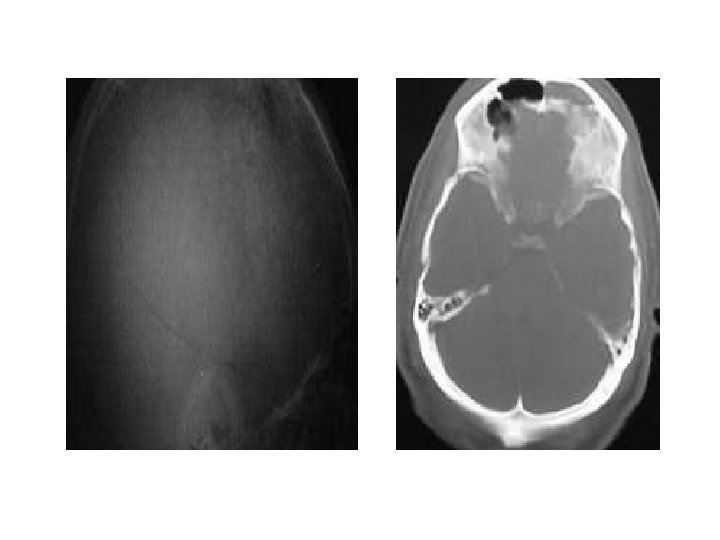

Depressed fracture